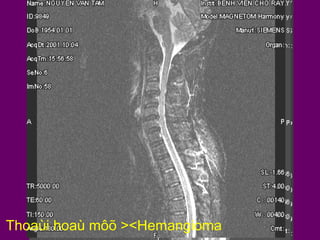

Thoaùi hoaù môõ ><Hemangioma